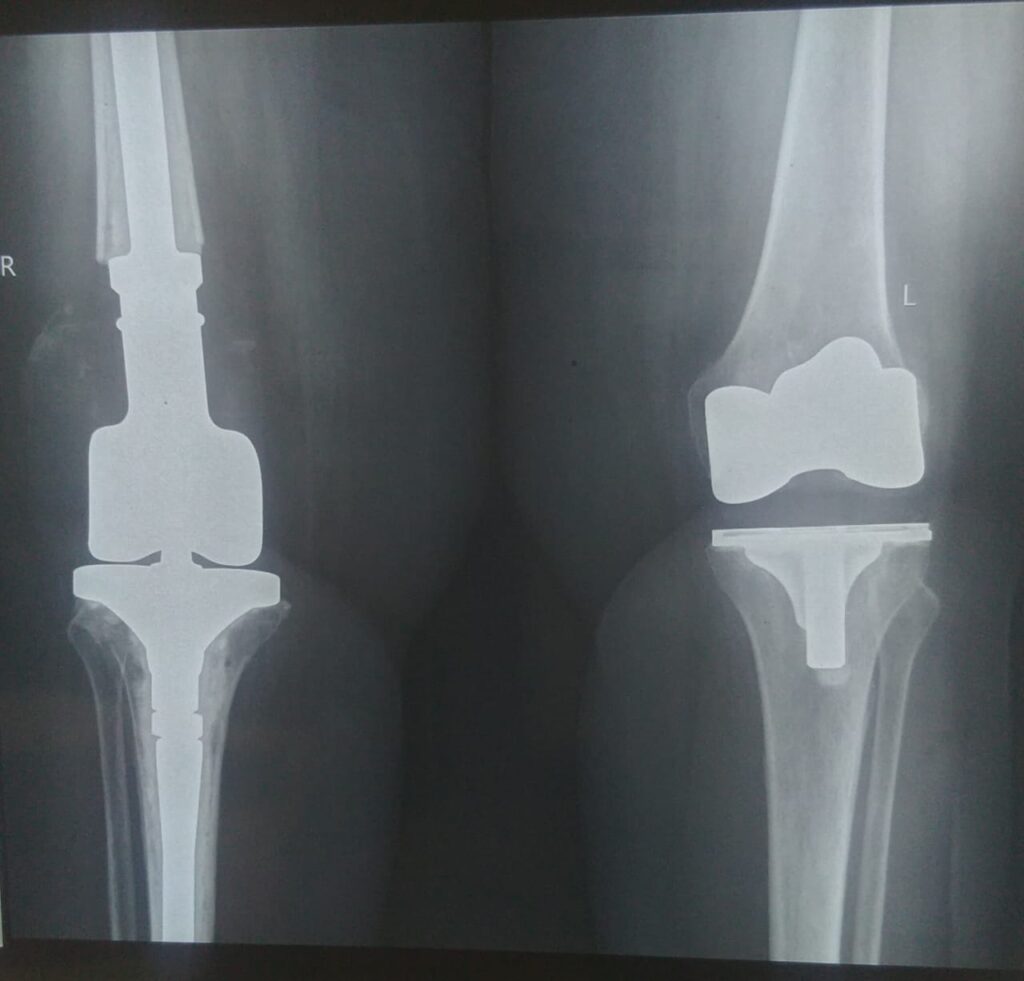

Revision Knee Replacement

When the prosthesis is loose or bone is severely damaged, revision surgery is needed. Long-stemmed implants provide stability and allow early weight-bearing.

This method is preferred for extremely distal fractures or when previous fixation has failed. It restores knee function and reduces pain.

Structural Allografts and Distal Femoral Replacement

In severe cases with poor bone, surgeons may use structural allografts or replace the distal femur. This complex procedure restores stability but is usually reserved for low-demand patients.

It provides a long-term solution when conventional revision is not feasible. Recovery requires close monitoring and rehabilitation.